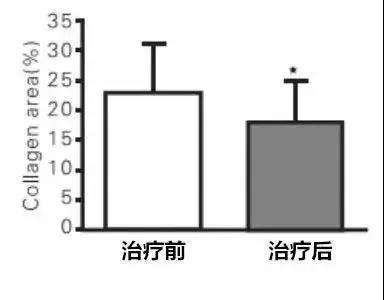

逆转肝脏纤维化

研究显示:干细胞可显著逆转患者的肝脏纤维化。

▲治疗前

▲治疗前

▲治疗后